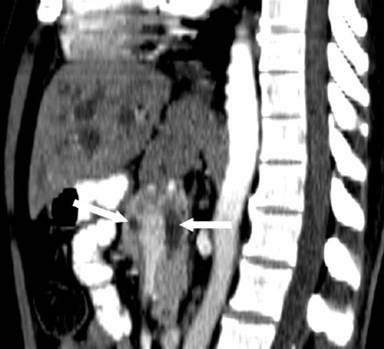

He underwent a pancreaticoduodenectomy. On transecting the neck of the pancreas, there was a small duct (4 mm) on the cut surface anterior to the portal vein. While dividing the bulky uncinate process, which seemed to extend posteriorly and to the left of the portal vein, a dilated duct (10 mm) was encountered. This dilated duct was found to be continuous with the main pancreatic duct posterior to the portal vein. The anterior duct in the neck of the pancreas terminated a few centimeters within the body of the pancreas without communication with the main pancreatic duct. The large pancreatic duct encountered in the uncinate process resection was closed with interrupted 5/0 polypropylene sutures. The neck of the pancreas anterior to the portal vein was excised up to the dilated main pancreatic duct, well to the left of the portal vein. The main pancreatic duct was laid open and a side to side pancreaticojejunostomy was performed. The patient made an uneventful recovery from the surgery. A review of the CT scan showed the double ducts encircling the portal vein with the main pancreatic duct lying posteriorly to the portal vein (Figures 1, 2, 3 and 4).

Figure 4. White arrows showing the pancreatic ducts on either side of the portal vein. |